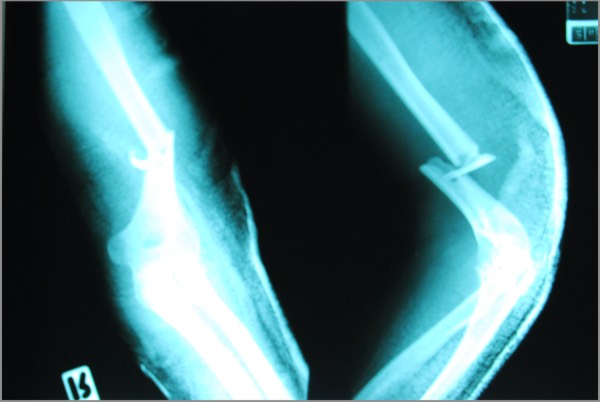

- severe closed comminuted fracture (4 fragments) of right upper humerus

- A very nasty upper arm (humerus) fracture, with multiple jagged pieces. The sharp edges seriously threatened major nerves and arteries, and the surgeon later spoke to me with great intensity about how arduous a job the repair had been: hours of holding Amy’s arm as perfectly still as possible. At the end of it she had a long steel bar screwed into her upper arm with several screws.